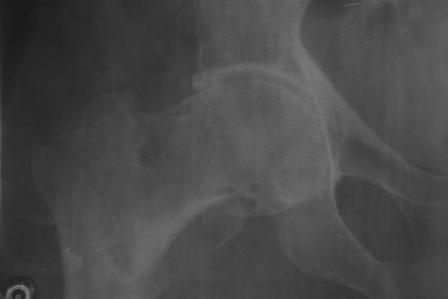

Доставлена больная 72 года. 3 дня назад упала. На R-грамме чрезвертельный простой АО 31А1 перелом левой бедренной кости. Кроме того имеется подозрение на субкапитальный 31В1 перелом , у меня на практике такое впервые. Трижды сделали R-графию, но качественный снимок не получилось. КТ в диагностическом центре на ремонте. 1. Действительно, имеется ли субкапитальный перелом, или мне так кажется? 2. Если да, то что можно делать? В наличии имеется длинные спонгиозные винты, большие расширяюшиеся в конце винты ЦИТО, Г- образные и продольные пластины АО, пластина Троценко-Нуждина, и мыщелковые пластины, заимствованные у Джолдаса. С уважением Абдурашид.

Мне представляется, что вопрос о переломе шейки тут не имеет большого практического значения. Шейка с головкой находятся в правильных взаимоотношениях, и это хорошо. При фиксации вертельного перелома фиксатор должен пройти в головку, так что она будет так или иначе фиксирована.

Складывается впечатление о перелома на фоне коксартроза. Соберите получше анамнез ( боли в суставе и т.д.) Мы бы поставили DHS.